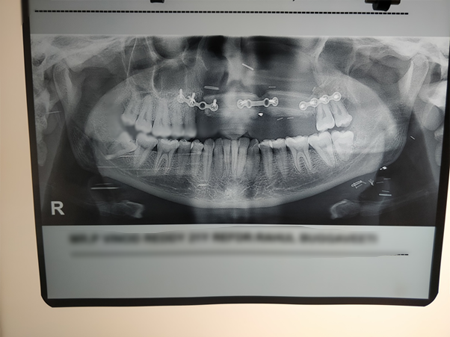

Young patient diagnosed with left maxillary sinus cancer (sarcoma)

Left partial maxillectomy done to clear tumor

Reconstruction done with fibula osteo-cutaneous free flap. So external shape is retained and floor of sinus reconstructed so that speech and swallowing are restored.

OPG shows osteotomies of fibula(reshaped leg bone)